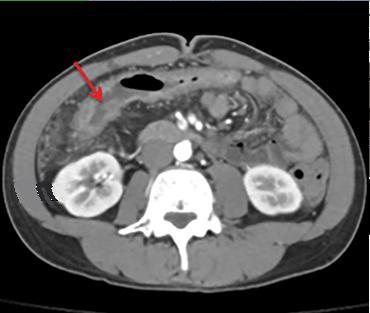

Aspect TDM du tuberculose ileocaecale est : Epaissisement

circumferentiel de la paroi ileum et caecum . Asymetrique

epaissisement de la valve ileocaecale .Mesenteric

lymphadenopathie et tuberculose pulmonaire est le plus

souvent .

Aspect de epaissisement

et stenosant de la paroi de ileon dans tuberculose

ileo-caecale( fleche rouge ) Image TDM en coupe axiale |

Epaissisement hyper-densite

de la paroi de ileon . Image TDM en coupe axiale |